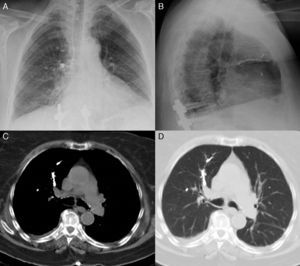

We report the case of a 76-year-old woman, operated 2 years previously for stenosis of the lumbar canal, with sequelae of sagittal imbalance and lumbar pseudoarthrosis. She was hospitalized to undergo T10-S1 arthrodesis with L3 percutaneous vertebroplasty. Six hours after surgery she developed dyspnea, tachypnea, and hypoxemia. On chest radiograph (Fig. 1A and B), dense ramified material was observed in the right upper, middle and lower lung fields and in the left middle field. On chest computed tomography (CT) (Fig. 1C and D), this material occupied the segmental arteries of the right upper, middle and lower lobes and the left upper lobe, and was diagnosed as pulmonary cement embolism (polymethylmethacrylate). She needed high-flow oxygen therapy for the first 24h, after which the oxygen component was gradually reduced until withdrawal a few days later. Pulmonary cement embolism is a potential complication after percutaneous vertebroplasty, due to extravasation of the cement injected into the vertebra to the paravertebral venous system, from where it can migrate to the pulmonary arteries.1,2 In cases of asymptomatic or peripheral embolism, the recommended approach is observation. Anticoagulant therapy, or even embolectomy, should be reserved for symptomatic cases or central embolism.2

Posteroanterior (A) and lateral (B) chest radiographs with dense ramified material, associated with cement emboli, in the right upper, middle and lower lung fields and the left middle field. On the chest CT cross-sectional slice (C and D), the same material occupies right upper lobe segmental arteries.